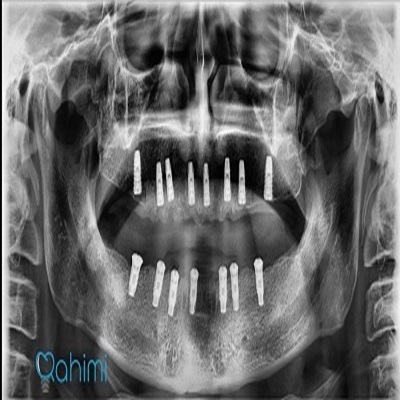

دکتر حامد رحیمی

دکتر حامد رحیمی متولد سال ۱۳۶۷ می باشند.ایشان در سال ۱۳۸۵ موفق به ورود به رشته دندانپزشکی دانشگاه علوم پزشکی تهران شدند و در سال ۱۳۹۱ فارغ التحصیل گردیدند.در سال ۱۳۹۴ پس از گذراندن طرح دوره دکتری عمومی در استان قم موفق به قبولی در رشته جراحی لثه و ایمپلنت دانشکاه علوم پزشکی تهران گردیدند.ایشان از سال ۱۳۹۷ و پس از کسب بورد تخصصی به عنوان عضو هیات علمی دانشگاه علوم پزشکی قم مشغول هستند.